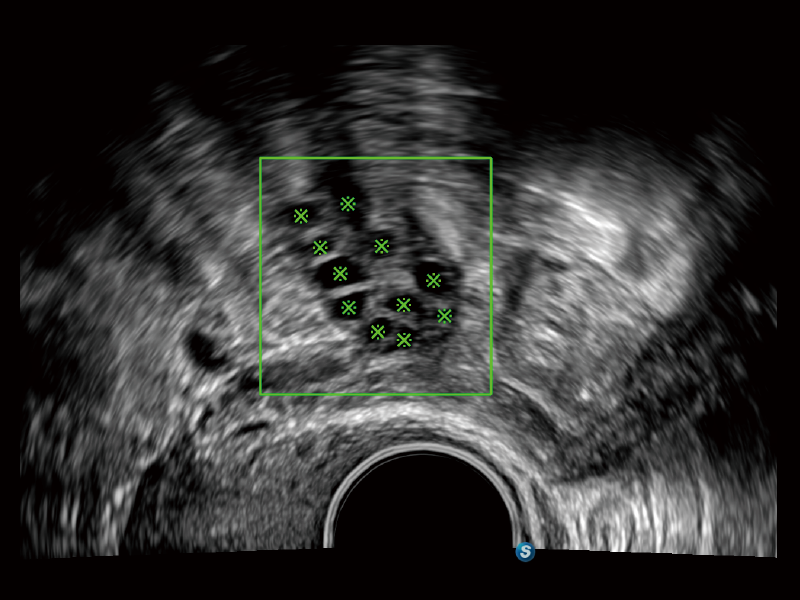

三維卵泡自動(dòng)測(cè)量

盆底自動(dòng)測(cè)量(2D)

盆底自動(dòng)測(cè)量(3D)